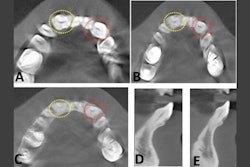

An intraoral x-ray of the patient's lower right mandibular area revealed a fused third molar and supernumerary tooth with an irregular morphology and a wide mesiodistal width. Radiopacity seen in the furcation area appeared to be the enamel pearl. Licensed by CC BY 4.0.He underwent an intraoral x-ray that showed fused molars with an irregular morphology and a wide mesiodistal width. The 2D view offered by the x-ray made it difficult to identify the demarcation between the pulp chamber of the third molar and the supernumerary tooth. Also, clinicians could not ascertain the root canal configuration of the tooth, according to the report.

Therefore, the man underwent a CBCT scan, which showed the pulp chamber was continuous, and the tooth had five canals. It had two orifices on the mesial, two in the middle, and one on the distal side.

Multiple CBCT slices revealed the unilateral fused third with a continuous pulp chamber. The axial view revealed the tooth had five canals.After discussing options with the patient, the patient chose to undergo nonsurgical root canal treatment for the fused molar. Once the root canal was completed, an x-ray was taken, and the tooth was restored with a temporary filling. The patient was told to undergo a full coverage restoration at his general dentist within a week, which he completed, they wrote.

An intraoral x-ray shows (A) a postoperative x-ray of the man's fused third molar with supernumerary tooth and (B) a six-month follow-up x-ray that shows normal bone appearance.Using all available diagnostic tools